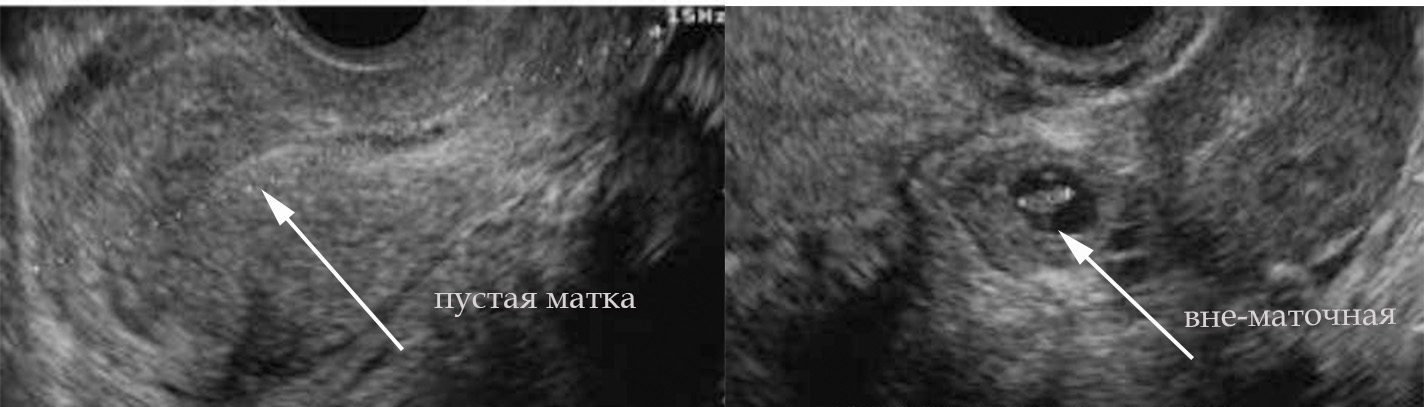

Узи рубец на неделе беременности - фото презентация